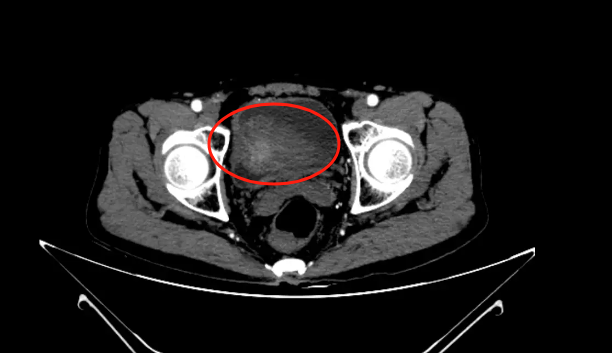

直肠肿瘤侵犯膀胱

术中,泌尿外科通过膀胱镜检查,发现冯先生的直肠肿瘤尚未侵犯到膀胱输尿管等重要结构,但在膀胱其他位置也偶然发现了原发肿瘤。

有了泌尿外科的检查,普外科为冯先生行 直肠癌扩大根治、膀胱部分切除、膀胱肿瘤切除、右半结肠根治等手术。